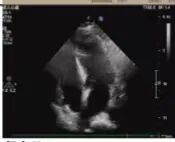

術后超聲

病理診斷

醫學協作創造生命奇跡

術后病理顯示,患者左房腫瘤為良性黏液瘤,完整切除后無需后續治療。經過10天的康復治療,老人順利出院。這一案例中,多學科團隊通過術前風險分層、術中精密協作、術后個體化護理,為高齡復雜心臟疾病患者的救治積累了臨床經驗